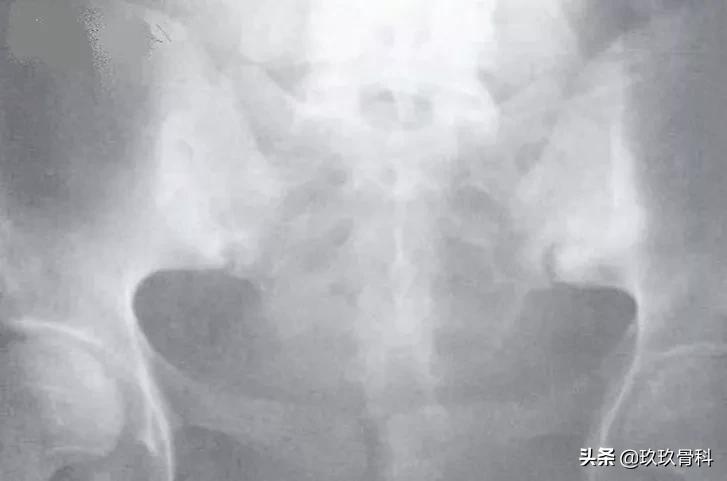

强直性脊柱炎(Ⅲ级)

图注:双侧骶髂关节,骨质破坏,髂骨侧软骨下致密硬化伴囊变,关节间隙狭窄。